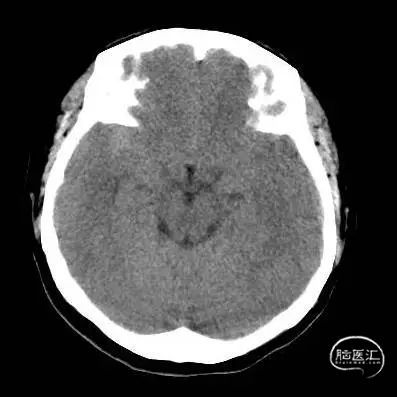

术前头部CT:

根据造影结合患者头部CT出血分布考虑朝上方的较大动脉瘤(1.3mm*1.2mm)为破裂出血的责任动脉瘤,但是其瘤体小难以致密填塞,并且朝下的微小动脉瘤约0.8mm,难以进行弹簧圈填塞,故考虑破裂动脉瘤予以1枚弹簧圈疏松填塞加快瘤内血栓形成后置入密网支架覆盖上下两枚动脉瘤进行血管壁修复。